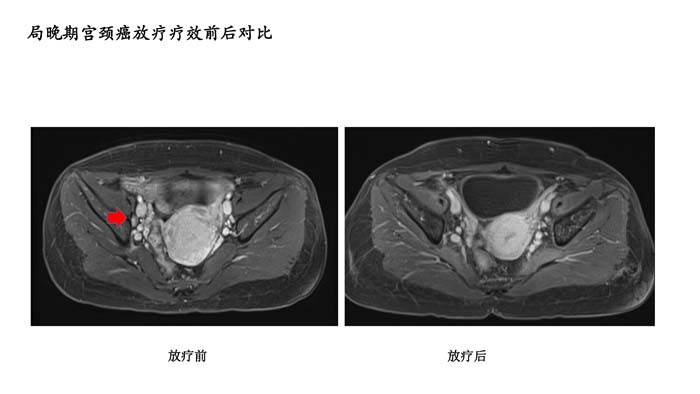

下一篇: 局晚期宫颈癌放疗疗效前后对比4